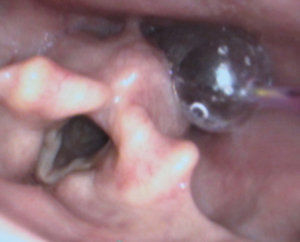

Depending on anesthesia level and other patient factors, the surgeon may perform the dilation in different ways. These include using instruments inserted through the mouth or nose, and using different dilators such as tapered cylindrical dilators or small balloons (see pictures below). The procedure usually takes about thirty minutes, and the most common side effect is a mild sore throat after surgery. Rare, though potentially serious complications include causing a small hole in the esophagus.

| Esophageal Dilation Tools | Example of Esophageal Dilation | |